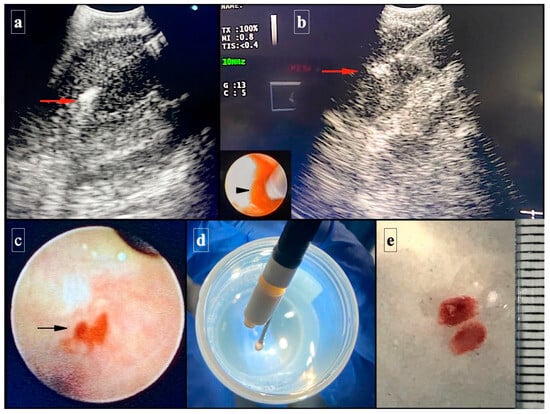

2.1. Technical EBUS-TBCNB Procedure